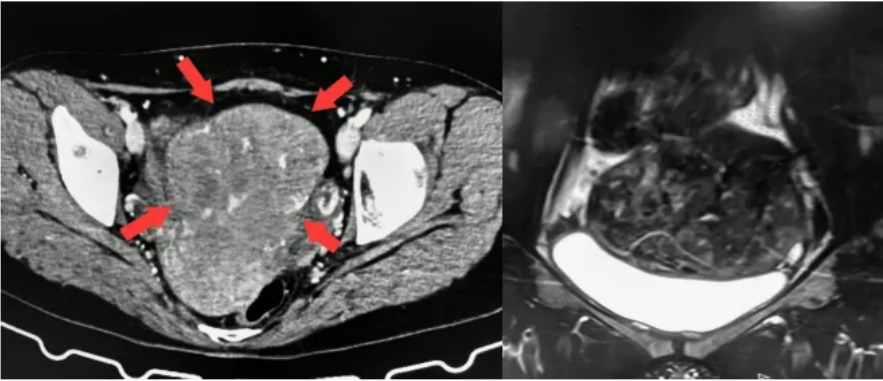

(▲盆腔CT及MRI,患者多发子宫肌瘤,膀胱压迫明显)